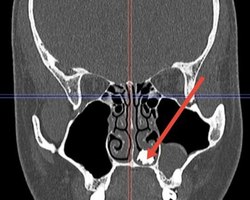

Врачи Долгопрудненской больницы достали из носа 22-летнего молодого человека молочный зуб. Он обратился с жалобами на продолжительный насморк. Проведенная диагностика выявила, что в полости носа пациента присутствует образование костной плотности.

— Во время операции, которую выполнили отоларингологи стационара Наиля Вихарева и Елизавета Ершова, был извлечен неизвестно как попавший и неизвестно, сколько пролежавший в носовой полости, покрытый грибковым содержимым молочный зуб, — сказал заместитель главного врача Долгопрудненской больницы по хирургии Евгений Кутырев.